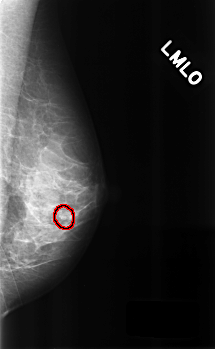

C_0300_1.LEFT_MLO

LEFT_MLO LINES 4528 PIXELS_PER_LINE 2792 BITS_PER_PIXEL 12 RESOLUTION 50 OVERLAY

FILE: C_0300_1.LEFT_MLO.OVERLAY

TOTAL_ABNORMALITIES 1

ABNORMALITY 1

LESION_TYPE CALCIFICATION TYPE PLEOMORPHIC DISTRIBUTION CLUSTERED

ASSESSMENT 4

SUBTLETY 3

PATHOLOGY BENIGN

TOTAL_OUTLINES 1

BOUNDARY